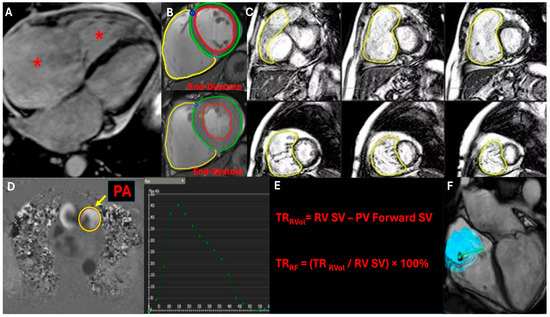

| Cardiac Magnetic Resonance (CMR) | Gold standard for right ventricular function and volume assessment. Provides accurate quantification of TR severity, regurgitant volume, and right ventricular ejection fraction (RVEF). Useful for assessing myocardial fibrosis and tissue characterization [24,25]. | Highly accurate and reproducible quantification of TR severity, right ventricular volumes, and function. Provides detailed tissue characterization, enabling assessment of myocardial fibrosis, which is critical in advanced heart failure patients [24,25]. | Limited availability, high cost, and longer acquisition time. Requires patient cooperation and breath-holding. Contraindicated in patients with certain metallic implants or severe claustrophobia [24,25]. |